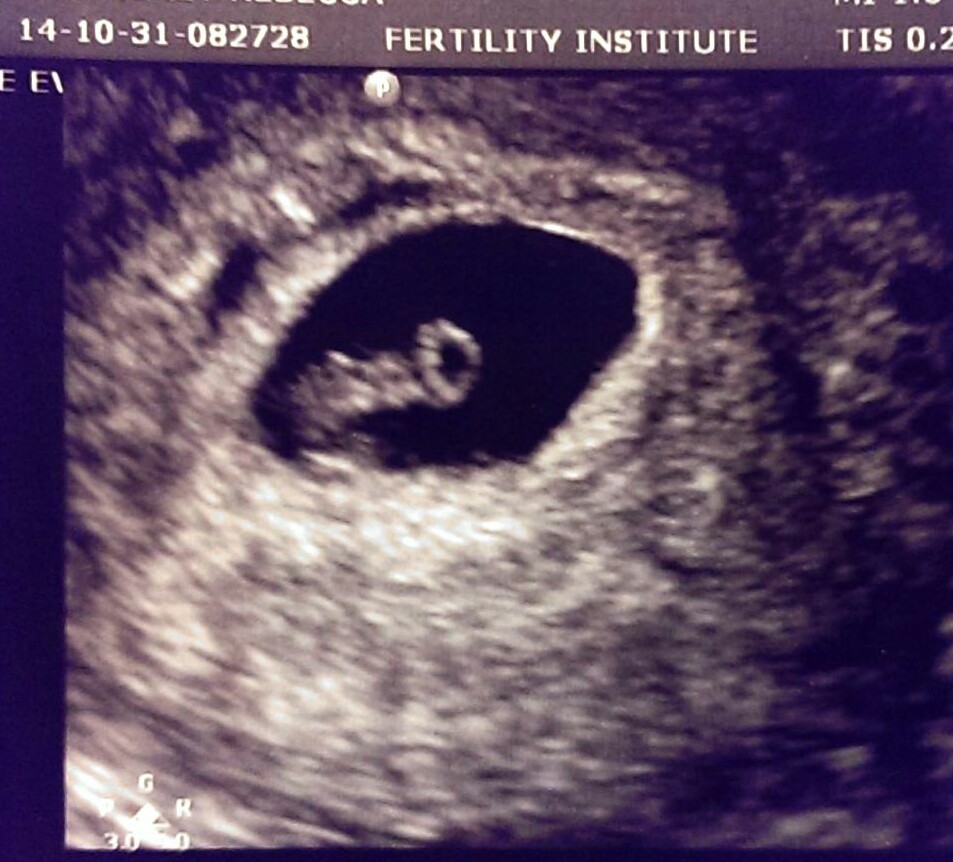

Lap & hysteroscopy scheduled for 10/31, right tube cleared, no endo found! ...Happy Halloween!

Cycle 14: Clomid (50)+ IUI = BFP! EDD 9/16/14~ Rowan Elizabeth born sleeping at 17w4d on 4/12/14 due to IC.

Cycle 20: Clomid (50)+ IUI = BFP EDD 6/20, transvaginal cerclage 12/19, Carson Quinn born sleeping at 16w3d on 1/6/15 due to IC